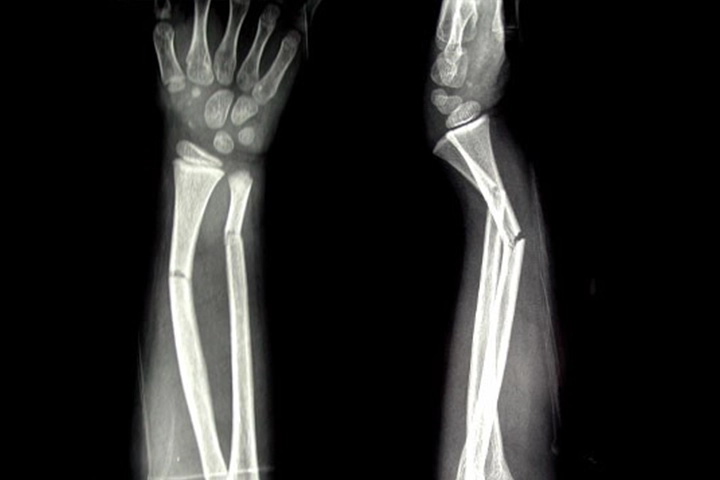

Fractures are diagnosed by an Orthopedic Trauma Surgeon. A detailed clinical examination followed by an X-ray to determine the extent of the break or damage to the bone helps diagnose a fracture.

- Upper limb fractures – Shoulder, Arm, Elbow, Forearm, Hand, & Wrist